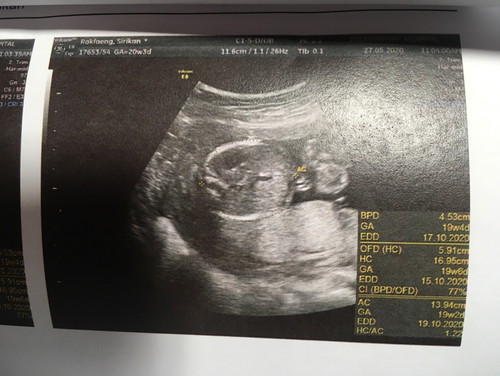

ไม่ได้ฟังเสียงหัวใจน้อง ไม่ได้ดูน้องในจอ แม่ตื่นเต้นเก้อเลยนึกว่าจะได้เห็นลูกดุ๊กดิ๊กในจอ หมอบอก ผญ 70% ดีนะแม่ยังพอได้ถามว่าน้องครบไหม สมบูรณ์ไหม ปกติไหม หมอบอกเท่าที่ดูก็ไม่มีอะไร งื้ออออ น้ำหนักตามเกณฑ์ ไว้เดือนหน้าแม่มีตังแม่จะไปซาวด์คลีนิค ยังดีได้รูปมาดู ❤️